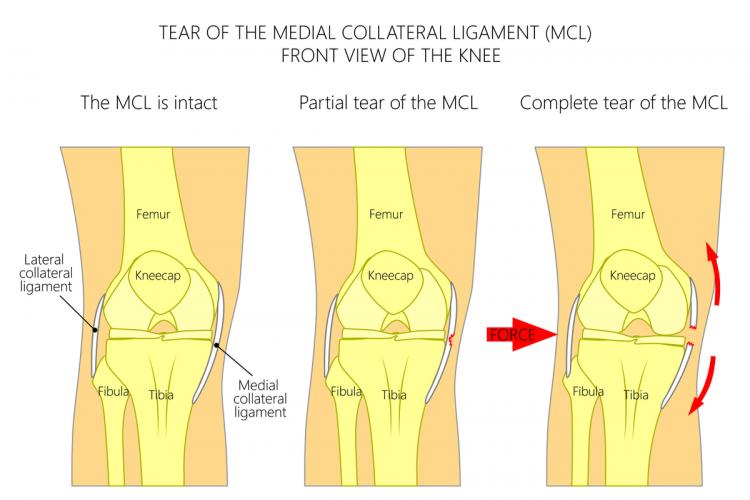

How to repair a torn mcl. Following your injury, the rice principle is commonly recommended to get the inflammation around the sprained. The surgery to correct a torn knee ligament involves replacing the ligament with a piece of. Van thiel to access the entire.

There are two primary types of mcl surgery: While most mcl injuries can resolve without surgery, there are instances where surgery is the best treatment option. You’ll need to raise your sore knee when you put ice on it, keep weight off the joint, and protect and compress the injury with a knee brace or elastic bandage.

Treatment options for an mcl sprain. The surgery will either repair or reconstruct the mcl. A total rupture of the mcl usually doesn’t require surgery.